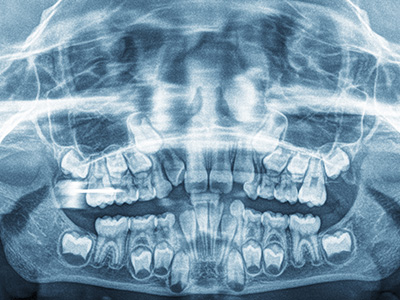

A cephalometric X‑ray is a specialized radiographic image that captures the entire head from the side, showing the relationship between the teeth, jaws, and skull. Unlike routine dental bitewings or panoramic radiographs, a cephalometric image provides a lateral profile that helps clinicians visualize skeletal patterns, tooth positions, and soft tissue contours in one plane. This single view is especially useful in orthodontic and growth‑related evaluations because it reveals how the skeletal and dental structures interact as a child develops.

This type of imaging is not intended to diagnose tooth decay; rather, it focuses on alignment, jaw relationships, and how the teeth sit within the facial skeleton. Orthodontists and pediatric dentists use cephalometric X‑rays to assess whether a child’s bite is balanced, whether there is a tendency toward underbite or overbite, and how facial proportions may change over time. The image serves as a baseline that can be compared with later images to track growth or treatment progress.

A cephalometric x-ray is a lateral skull radiograph that captures the relationship among the teeth, jaws and cranial skeleton in a single profile view. Clinicians use this image to evaluate skeletal pattern, dental inclination and soft tissue contours that are not visible on intraoral films alone. The image provides an objective baseline that helps guide timing and type of orthodontic or growth-related interventions.

Because it shows the entire head in one plane, a cephalometric study is particularly helpful for understanding how a child’s facial proportions may change as they grow. It complements clinical examination and other imaging to produce a more complete diagnostic picture. When interpreted alongside growth data and dental models, the film supports individualized treatment planning that balances function and facial aesthetics.

Cephalometric x-rays are taken from the side of the head and emphasize skeletal relationships and facial proportions, while panoramic and bitewing radiographs focus on teeth, tooth roots and jawbone in different planes. Panoramic images show the entire dentition and jaw arches on a single curved plane, and bitewings are designed to detect interproximal decay and bone levels. Each radiograph has a different diagnostic role, and cephalometric images are chosen when skeletal and growth considerations are primary.